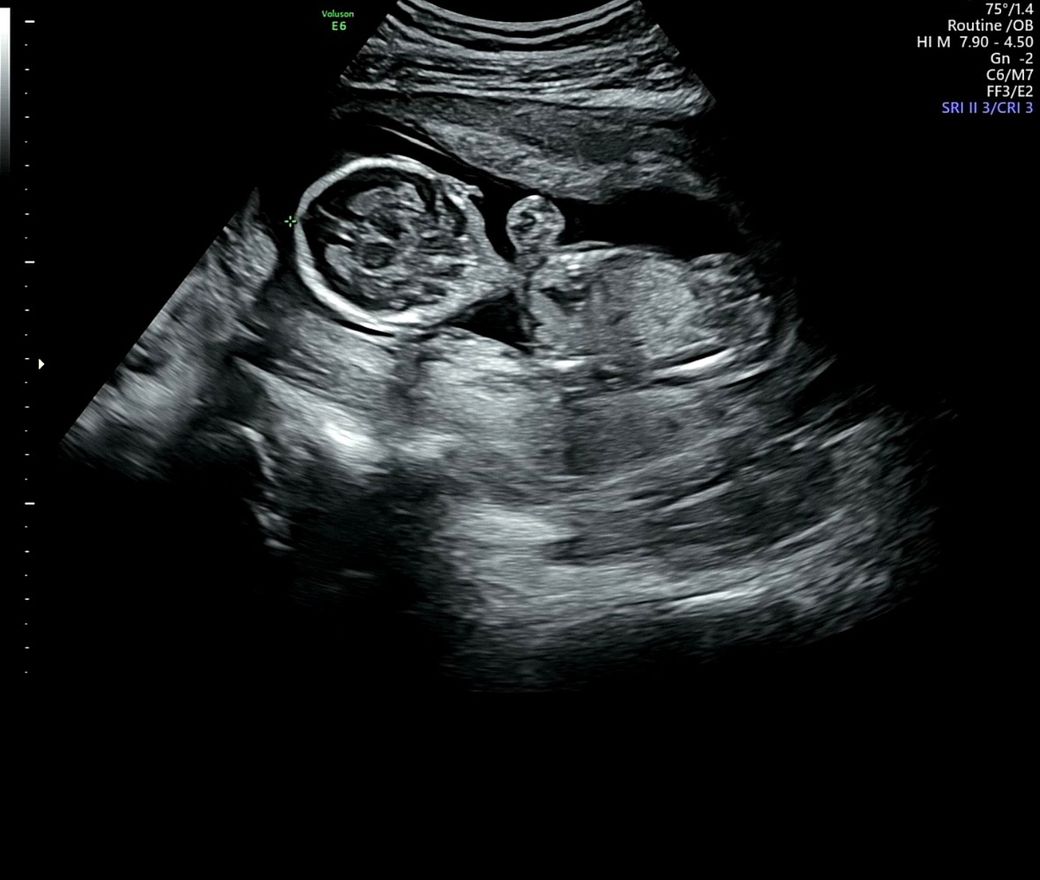

16주에 2차 기형아 검사 결과로 신경관결손 얘기를 들았고 수치는 6.4….나왔습니다.양수검사 받아보라고 병원에서 얘기했으나 양수검사는 받지 않기로 마음먹고 서울 대학병원 정밀초음파 예약 잡아놓은상태입니다..아직 예약일까지 3주 가까이 남아서 숨이 턱턱 막히고 하루하루가 불안하지만 아기를 믿고 운명을 믿는수밖에 아무것고 할수 있는게 없네요.. 기존 산부인과 선생님도 초음파 다시 돌려보면서 혹시 본인이 놓친것이 있나 다시 봤는데 문제는 없어보였으나 아직 아기가 너무 작아서 안보일수도 있다고 하더라고요.. 대학병원 예약일에는 19주 5일 예정입니다..온라인상으로는 질문 안하고 싶었으나 하루하루가 너무 초조해서 글남겨 봅니다전문의 분들 보시기에 아기 머리 모양에 의견을 구할 수 있을까요?

• 1번 째 사진